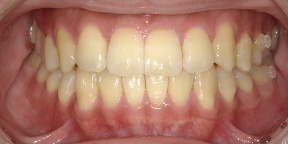

29歳女性のビフォーアフター

| 診断 | 叢生(デコボコがある状態)、過蓋咬合 |

| 治療方針 | インビザラインシステムにて主にIPR(歯と歯の間をわずかに削合してスペースを獲得する方法)を組み込んだ動的矯正治療を行い、叢生を改善後、保定を行う。臼歯部の咬合関係はプランの関係上維持して叢生と前歯部の咬合改善を目指した。 |

| 治療費 ※ | 60万4千円(診断、型取り、PMTC、保定装置を含む料金) |

| 治療期間 | 1年5か月 |